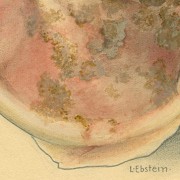

Lilly Ebstein Lowenstein (1897-1966) led a life between science and art, drawing and taking photographs in the fields of Medicine and Zoology. In her work, Lilly combined her technical knowledge of photography and drawing, the study of the sciences and a remarkable talent for aesthetics. She was born in Germany and studied at the Lette-Verein School in Berlin from 1911 to 1914. In 1925, she immigrated with her husband and two children to São Paulo. In 1926, she became an illustrator and photomicrographer at the Illustration and Photography Department at the School of Medicine (USP, as of 1934), which she headed for thirty years after 1932. Lilly collaborated at Instituto Biológico de Defesa Agrícola e Animal (the Biological Institute for the Defense of Agriculture and Animals), from 1930 to 1935, namely in the Avian Pathology Department. A life with art dedicated to the research and dissemination of science.